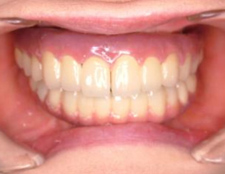

最終補綴物装着

【正面観】